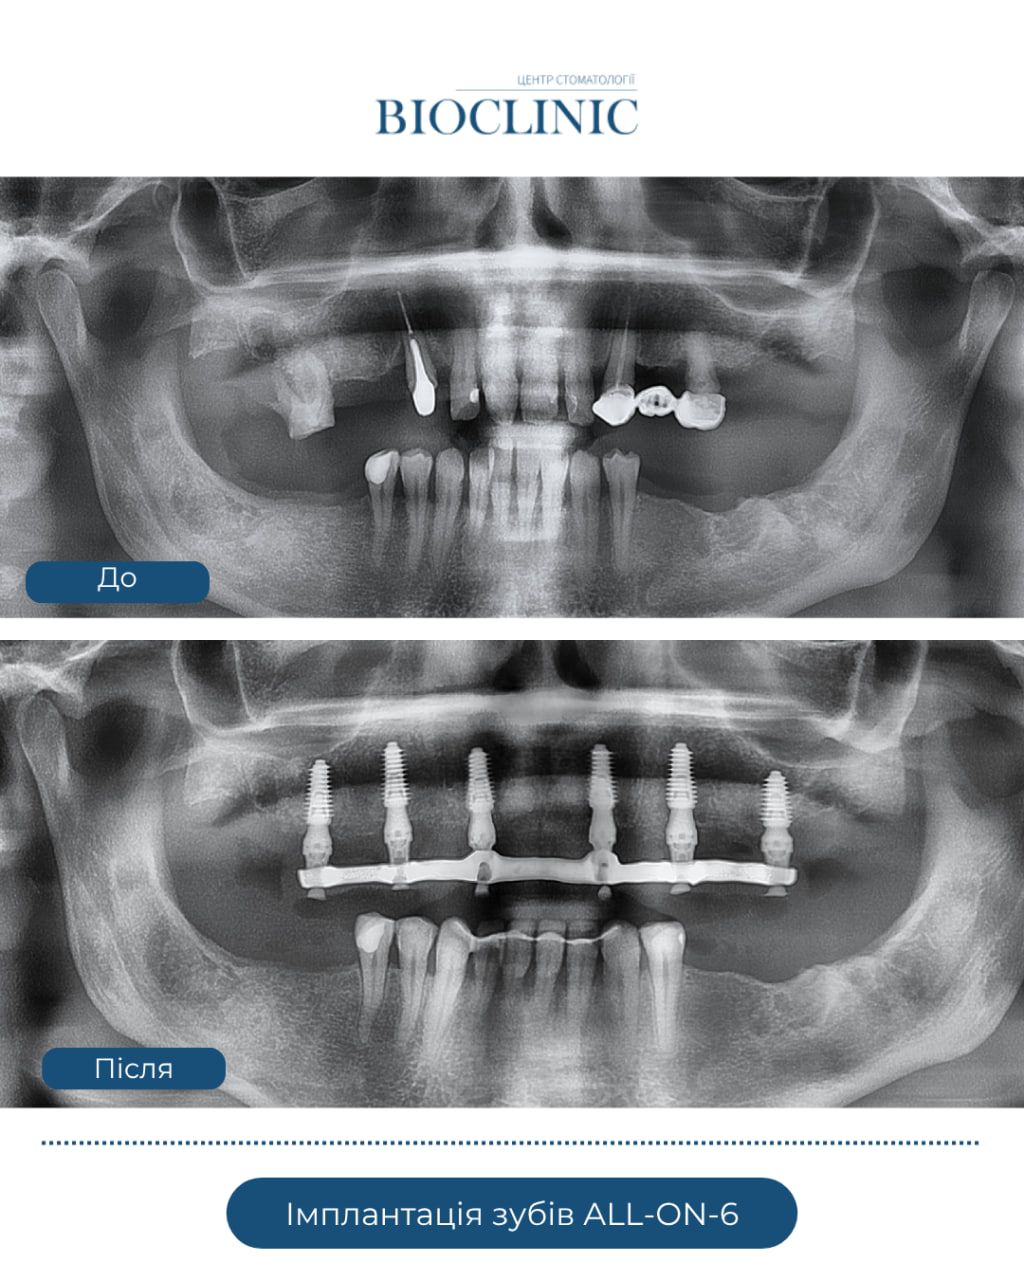

Технологія All-on-6, як пояснили стоматологи, дещо схожа з методом All-on-4. Вона дозволяє відновити повний зубний ряд за допомогою шести імплантатів та ідеально підходить пацієнтам, які повністю втратили зуби або мають серйозні проблеми з їхньою стабільністю. На відміну від знімних протезів, імплантація зубів All-on-6 забезпечує надійну фіксацію та природний вигляд.

У щелепну кістку встановлюють шість титанових імплантатів. Два з них – у фронтальну зону, де кісткова тканина зазвичай найщільніша, і чотири – у жувальній зоні. Такий розподіл забезпечує рівномірне жувальне навантаження та довговічність конструкції. У день операції пацієнту можуть встановити тимчасові протези, що дозволяє відразу повернутися до звичного життя.